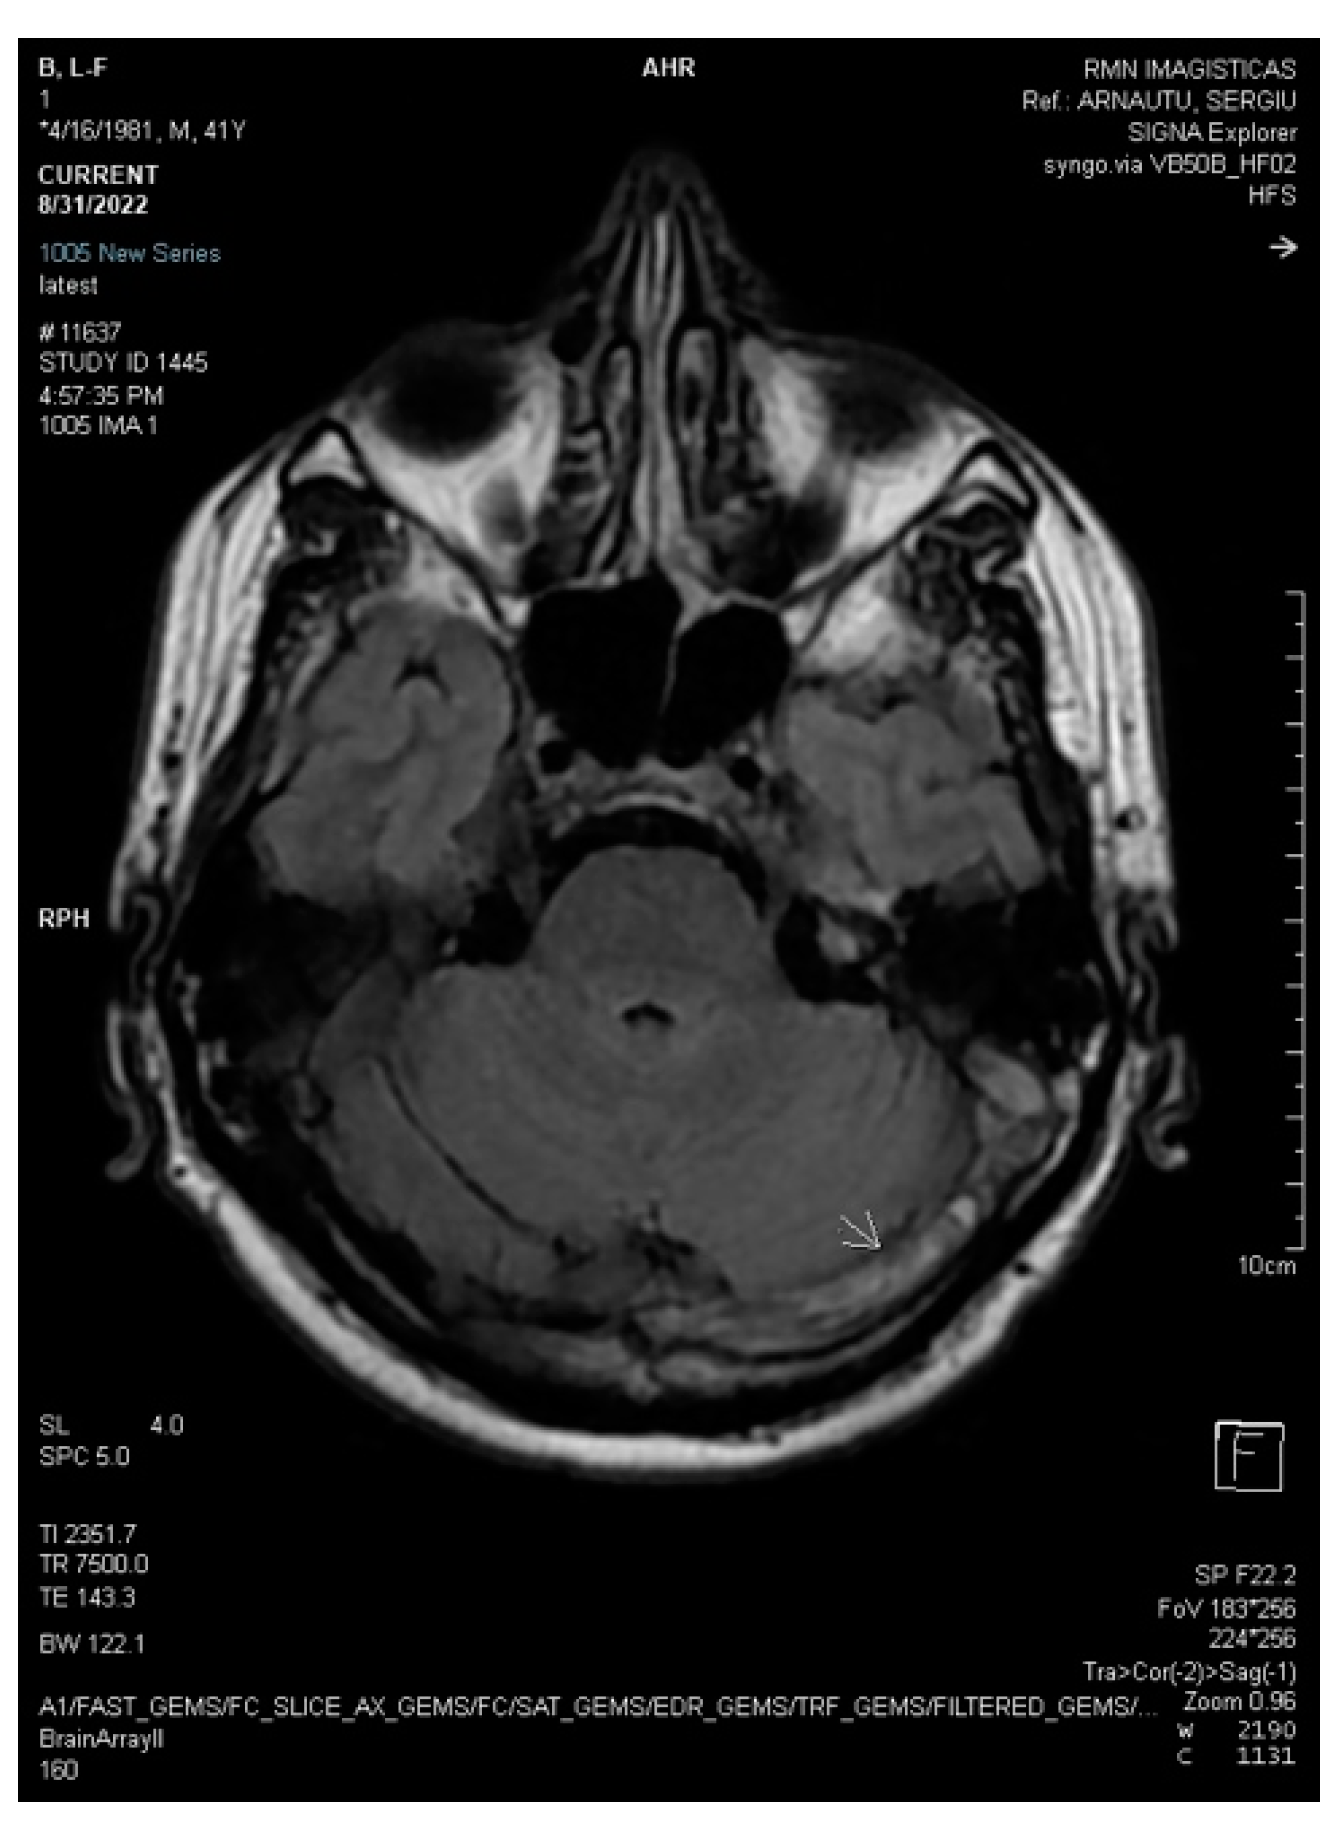

2.2. Neuroimaging Data